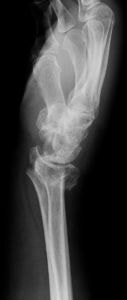

橈骨遠位端骨折と橈骨遠位端変形治癒骨折

Distal Radius Fracture and Malunion

橈骨遠位端関節内粉砕骨折の術前(上)と術後(下)

橈骨遠位端骨折は、通年ですべての年齢層において最も多い上肢の骨折の一つです。骨折の主な原因は、転倒や高所から転落して手をつくことですが、手を強く捻って受傷することもあります。本骨折は、ケガの仕方、外力の大きさや骨の強さにより折れる場所や折れ方に様々なタイプ(型)があるのが特徴であり、尺骨や手根骨の骨折、手関節の靭帯損傷や神経障害を合併することもあります。

治療法は、骨折の型、骨折の徒手整復の可否、そして合併症の有無により異なり、比較的軽いものには保存的治療が、変形が大きかったり粉砕していたり骨折が関節内に及ぶ重症例には手術が行われてきました。しかしながら、近年は一人暮らしのご高齢の方の増加により、さほど重症でない骨折に対しても、早期から手の使用を可能とし、後遺障害を少なくするために手術を行うことが多くなってきています。

手術には、経皮的に鋼線を刺入して固定するピンニングや骨折部を直視下に整復してプレート固定する観血的手術があります。術後には早期の機能回復を目的としてリハビリ(作業療法)を行うことがあります。

大きな変形を残して骨が癒合すると手関節の疼痛や手指の機能障害が残存したり、将来、二次性の変形性関節症を生じる原因となることがあります。骨の変形による症状を改善させるために、矯正手術(骨切術)が必要になることがあります。

『骨折したのだから障害が残っても仕方が無い』という考え方は過去のものです。将来なるべく不自由をしないために、きちんとした診断と適切な治療を受けられて下さい。新鮮な骨折はもちろん骨折後の障害についても、お気軽にご相談下さい!

橈骨遠位端変形治癒骨折の術前(左)と術後(右)